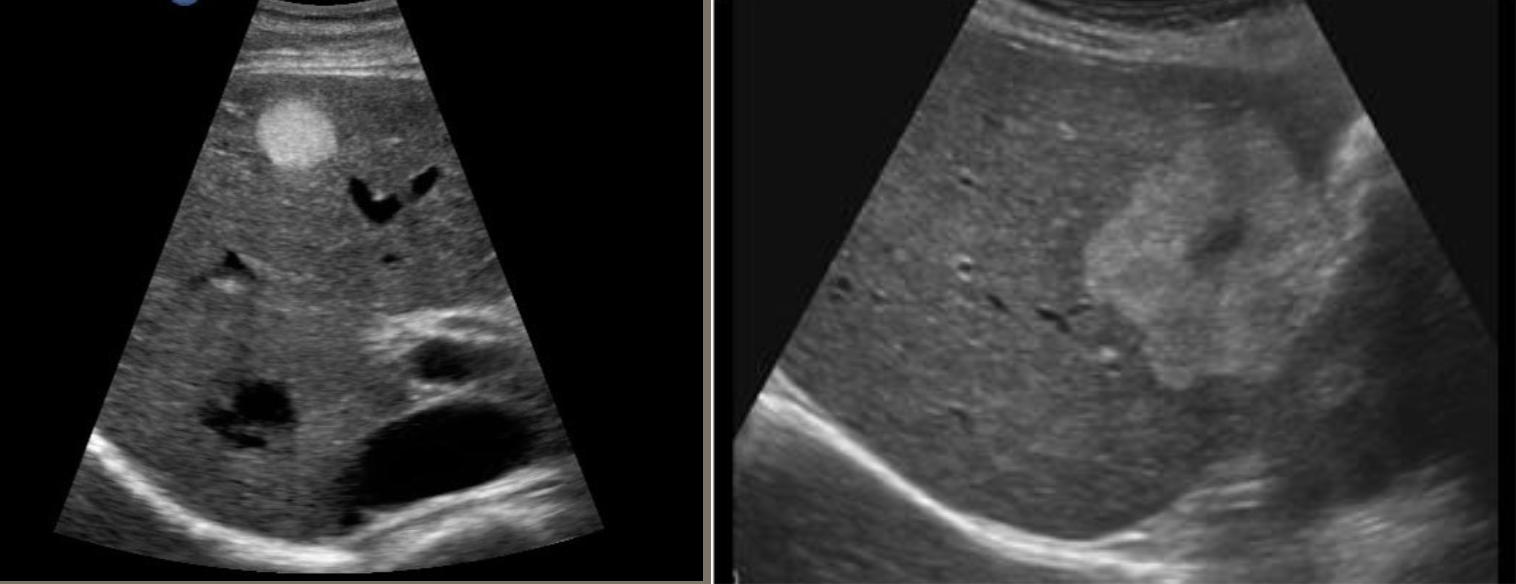

Cavernous Hemangioma → benign tumor of liver

clinical hx: adult female

s/sx: asymptomatic

2D US: typically small (can be large), less than 3 cm, well-defined, homogenous and hyperechoic, scalloped margins or can be heterogenous with hypoechoic center → larger = loses echogenicity w/ hypoechoic center → multiple = hemangiomatosis

color doppler: hypoperfused